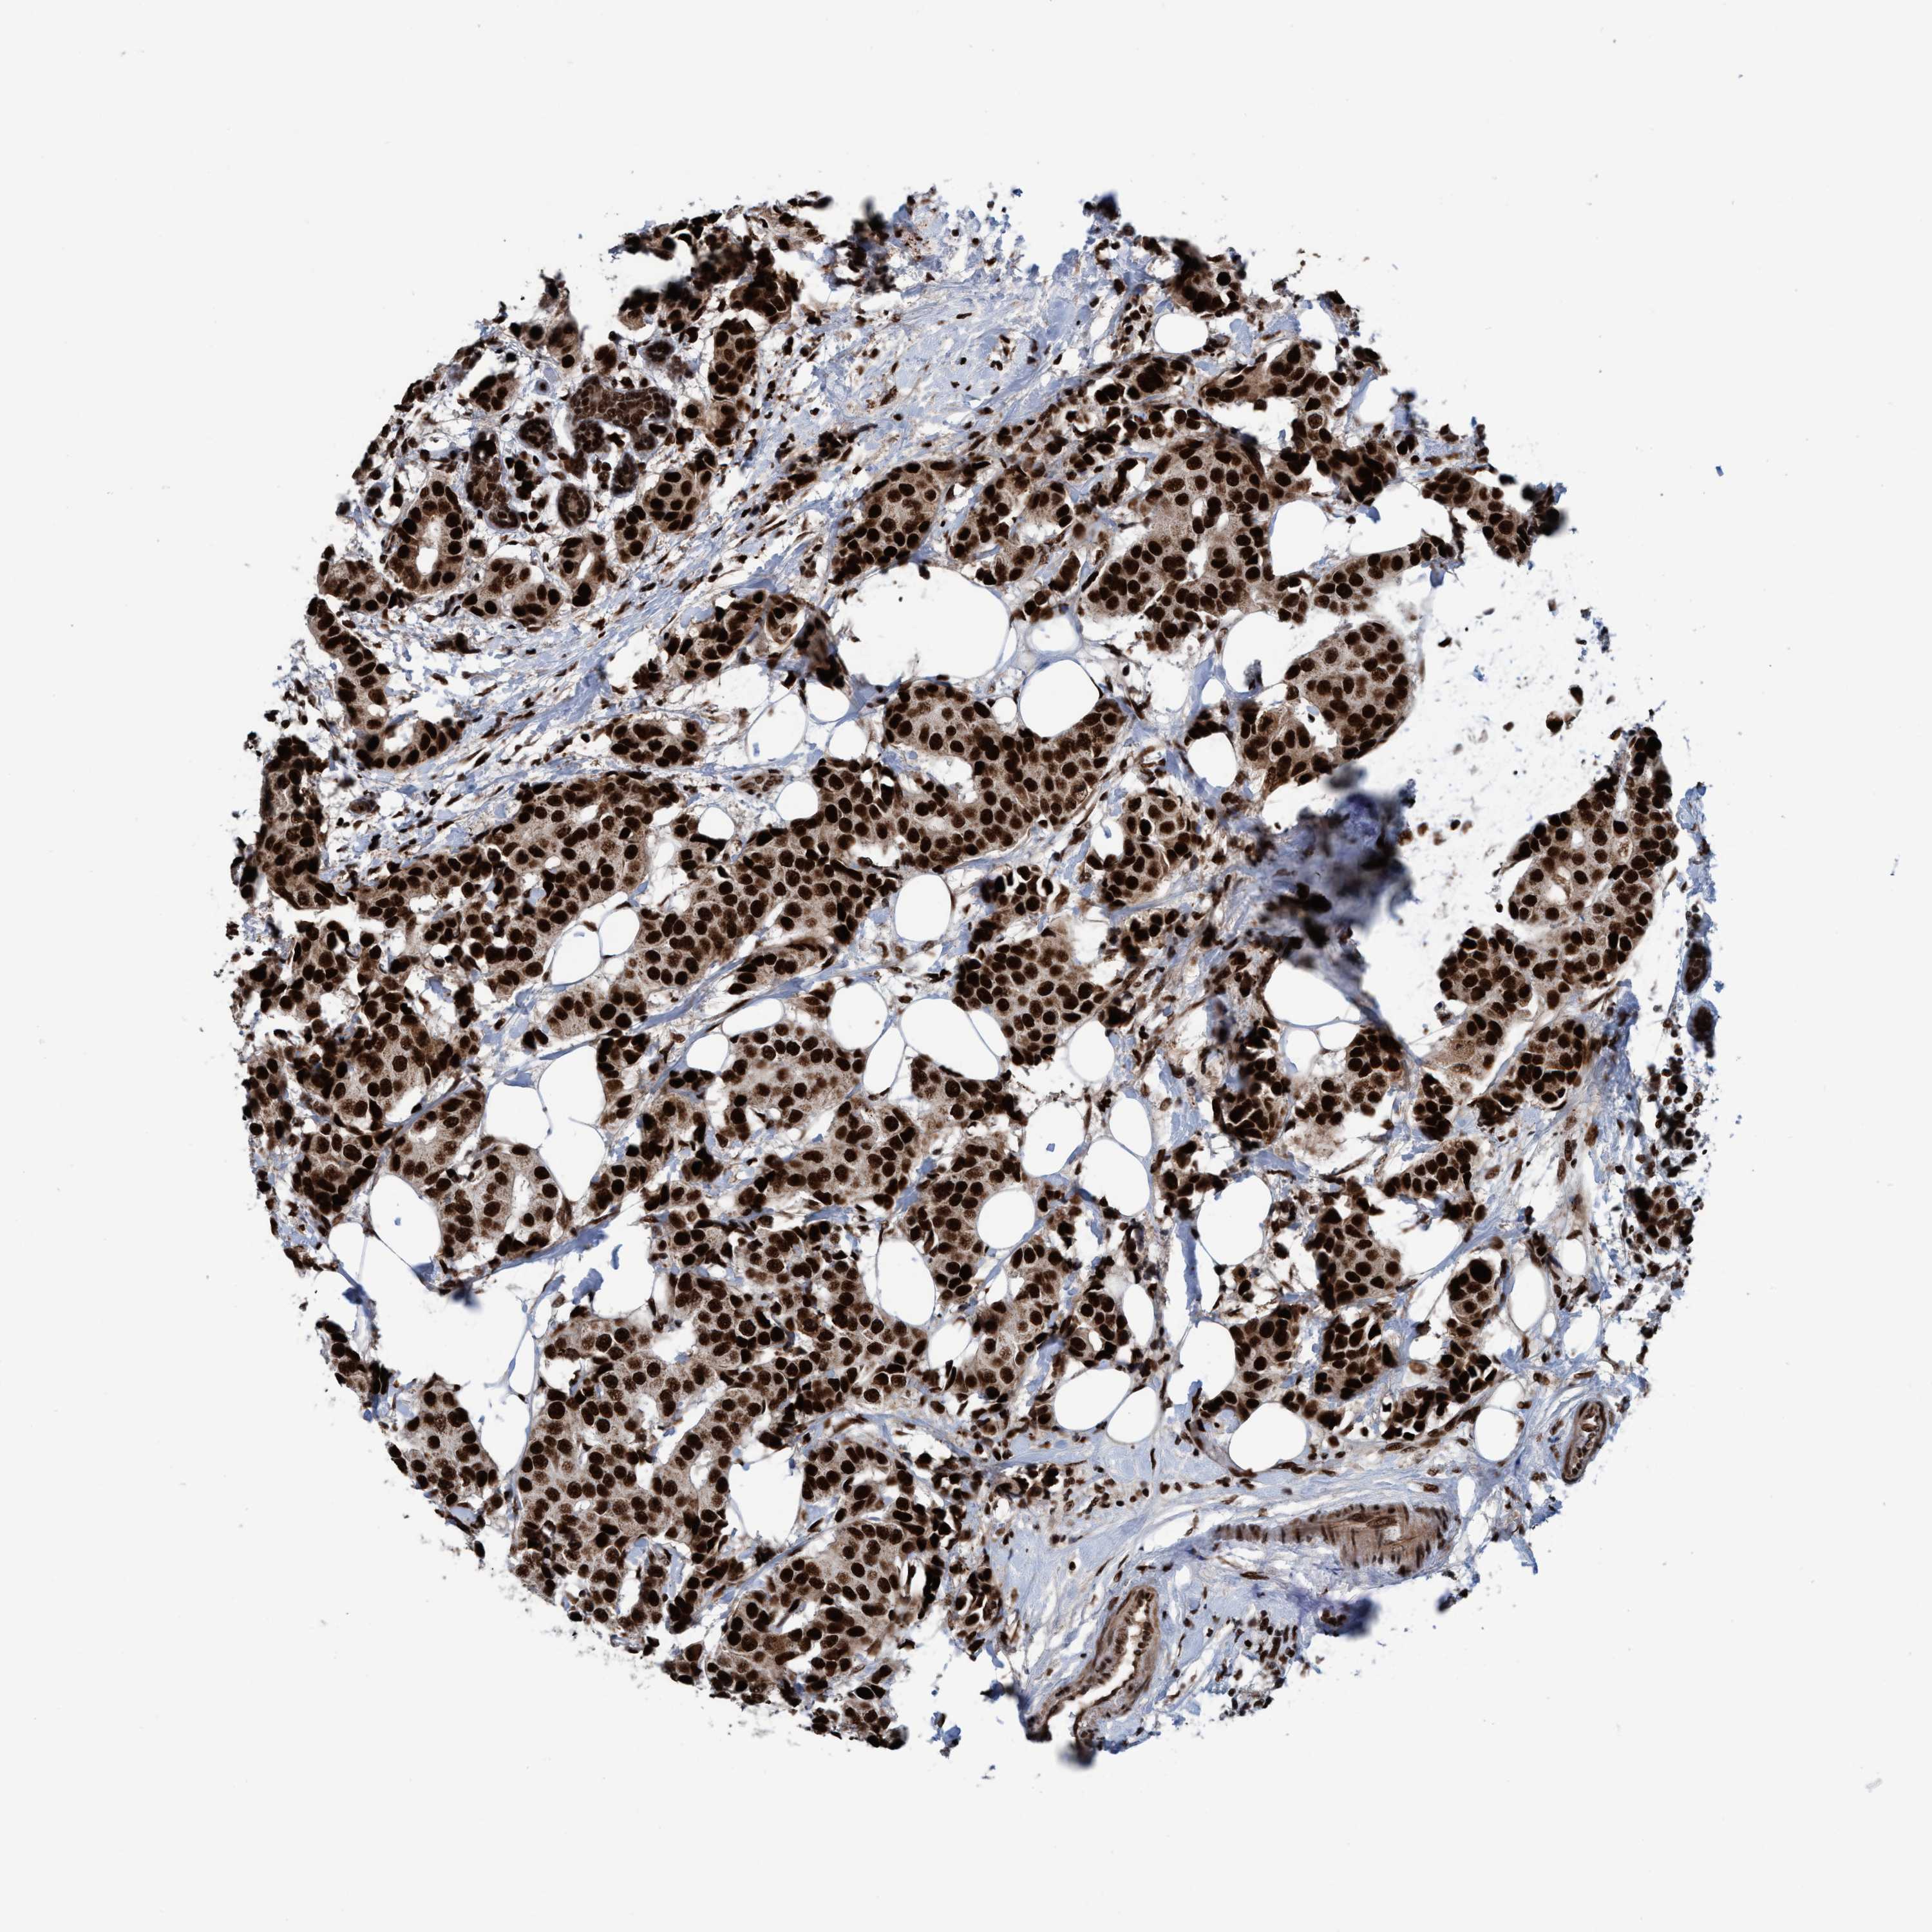

BRCA TCGA BRCA VALIDATION PROTEIN EXPRESSION